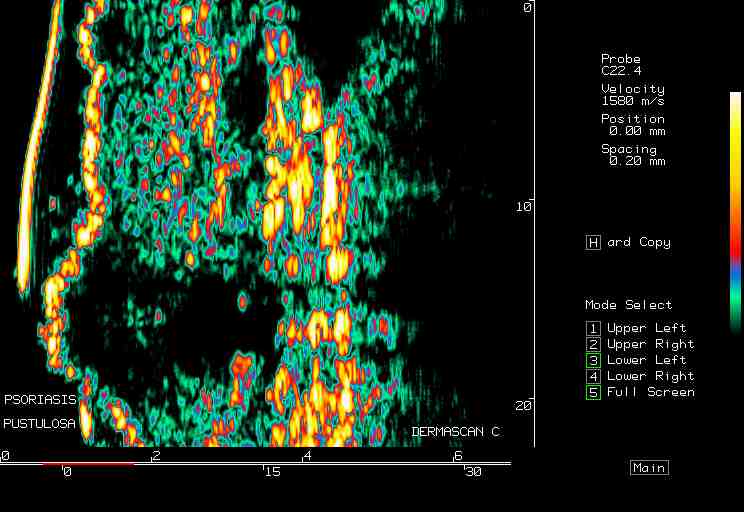

Pustular psoriasis |